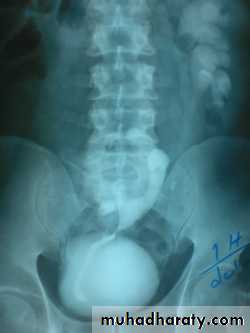

Ureterocele :

Congenital cystic dilatation of lower end of ureter ( intra-mural part) due to pin-hole meatus . May be simple or ectopic .

simple : the orifice is in proper position of bladder ,

Ectopic >> in bladder neck , urethra , uterus & vagina .

IVU :

- There is rounded or elliptical dilatation of lower end of ureter with thin lineal filling defect around it , resembling (cobra head appearance),

- Proximal dilatation of rest of ureter .

- In advanced cases hydronephrosis .

- In obstructed ureterocele , filling defect in the bladder